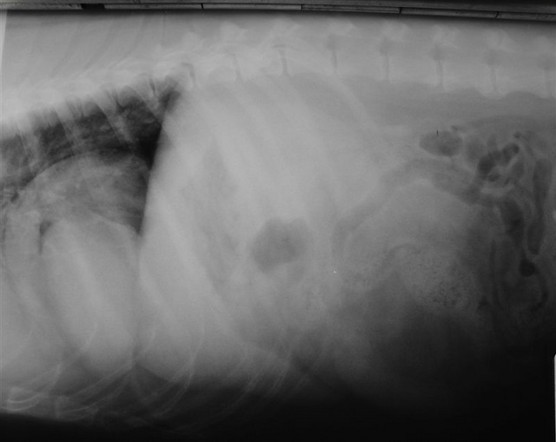

5

Radiography - Diaphragmatic hernia